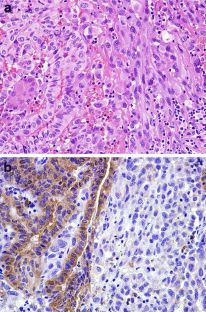

Raf-1 kinase inhibitory protein (RKIP) has been implicated in several fundamental signal transduction pathways that control cellular growth, differentiation, apoptosis and migration. RKIP is reduced in a variety of human carcinomas, but RKIP expression in thyroid carcinomas has not been analyzed at the protein level. In this study, we examined the immunohistochemical expression of RKIP in various subtypes of thyroid carcinoma. Immunostaining for RKIP was performed on 104 cases of primary thyroid carcinoma (40 papillary, 29 follicular, 11 medullary, 11 poorly differentiated, and 13 anaplastic carcinomas) and 26 cases of nodal metastatic tumor (17 papillary, 4 medullary, and 5 anaplastic carcinomas). Normal thyroid tissue and all cases of follicular, papillary, and medullary carcinomas showed uniform, strong cytoplasmic immunoreactivity for RKIP. With the exception of one case, poorly differentiated carcinomas also revealed strong RKIP expression. In contrast, RKIP expression was completely absent in all anaplastic carcinomas. The transition zone from the differentiated carcinoma component (strong RKIP expression) to the anaplastic carcinoma component (no RKIP expression) demonstrated a completely opposite pattern of RKIP immunoreactivity. This reduction of RKIP expression in anaplastic carcinoma was statistically significant (P < 0.0001). Additionally, RKIP expression of nodal metastatic tumors corresponded with that of primary tumors: metastatic papillary and medullary carcinomas showed uniform, strong cytoplasmic RKIP immunoreactivity, in contrast, in metastatic anaplastic carcinomas, RKIP expression was completely absent. RKIP expression is significantly reduced in anaplastic thyroid carcinoma as compared to other subtypes of thyroid carcinoma. Further studies are necessary to elucidate the precise mechanism of RKIP action in anaplastic thyroid carcinoma.

Fig. 1

Fig. 2

Fig. 3